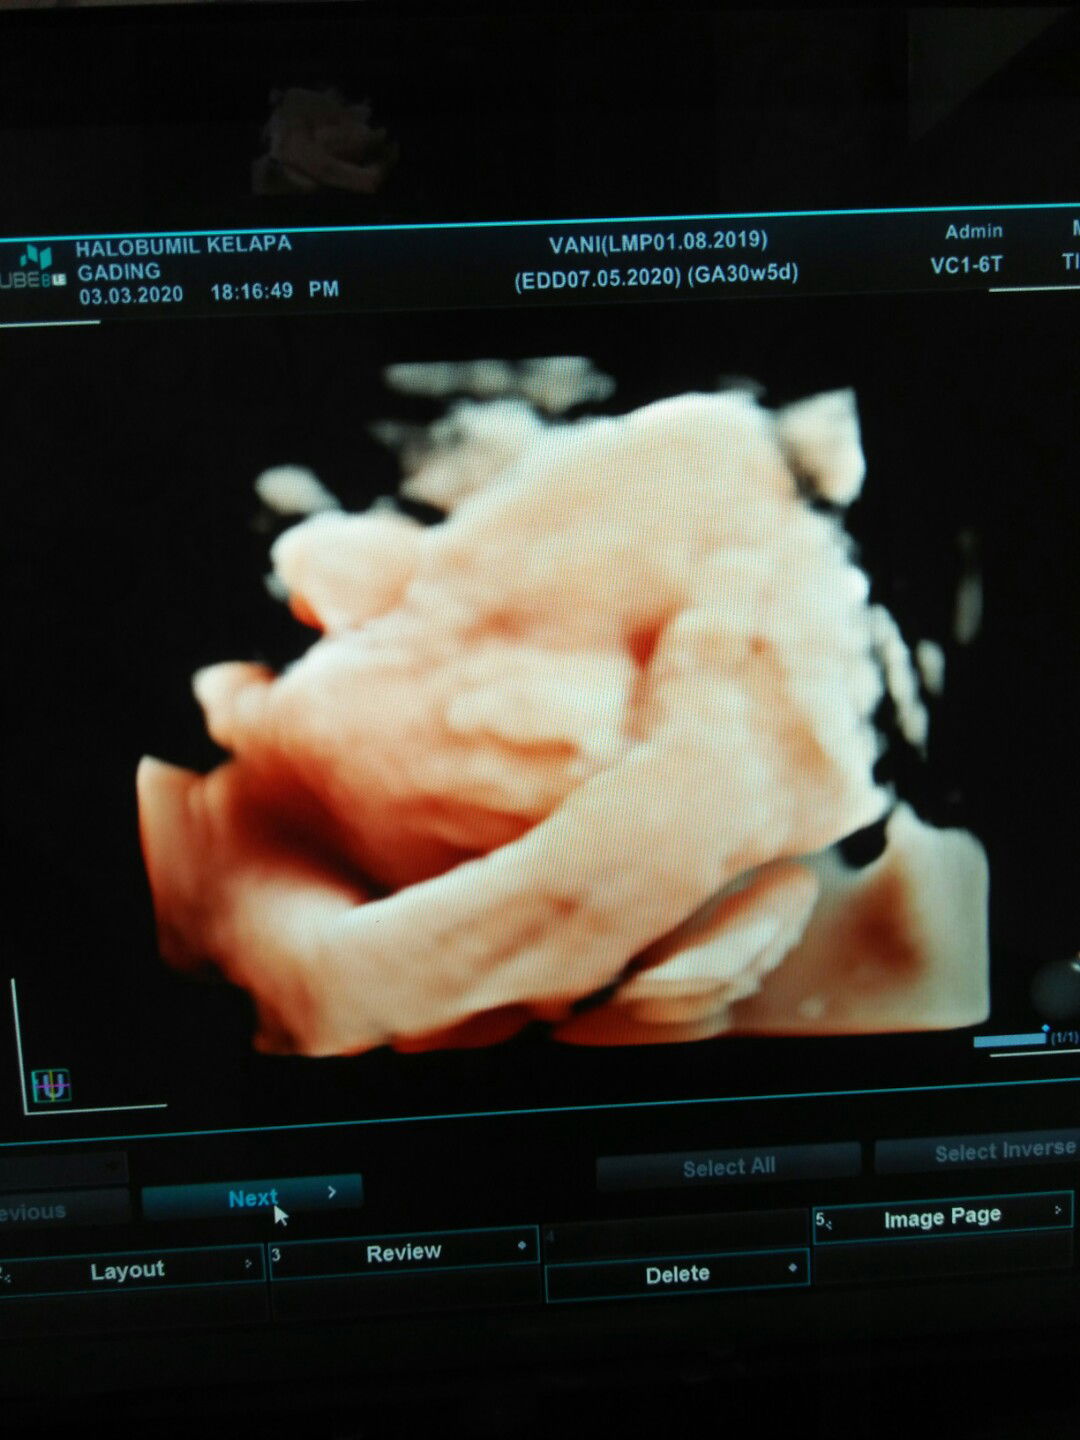

Vani Melo profile icon

Vani Melo

Wajaar bun